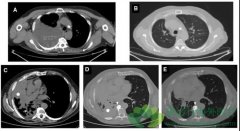

在驱动基因阳性的 非小细胞肺癌 患者中,有30%左右在初步诊断时就合并了脑转移,约有30%-50%的患者在后续治疗过程中会出现脑转移。针对脑转移患者的治疗模式正在逐步改变,90年代使用单纯的全脑放疗,90年代至2010年期间使用全脑放疗联合立体定向外科治 ...